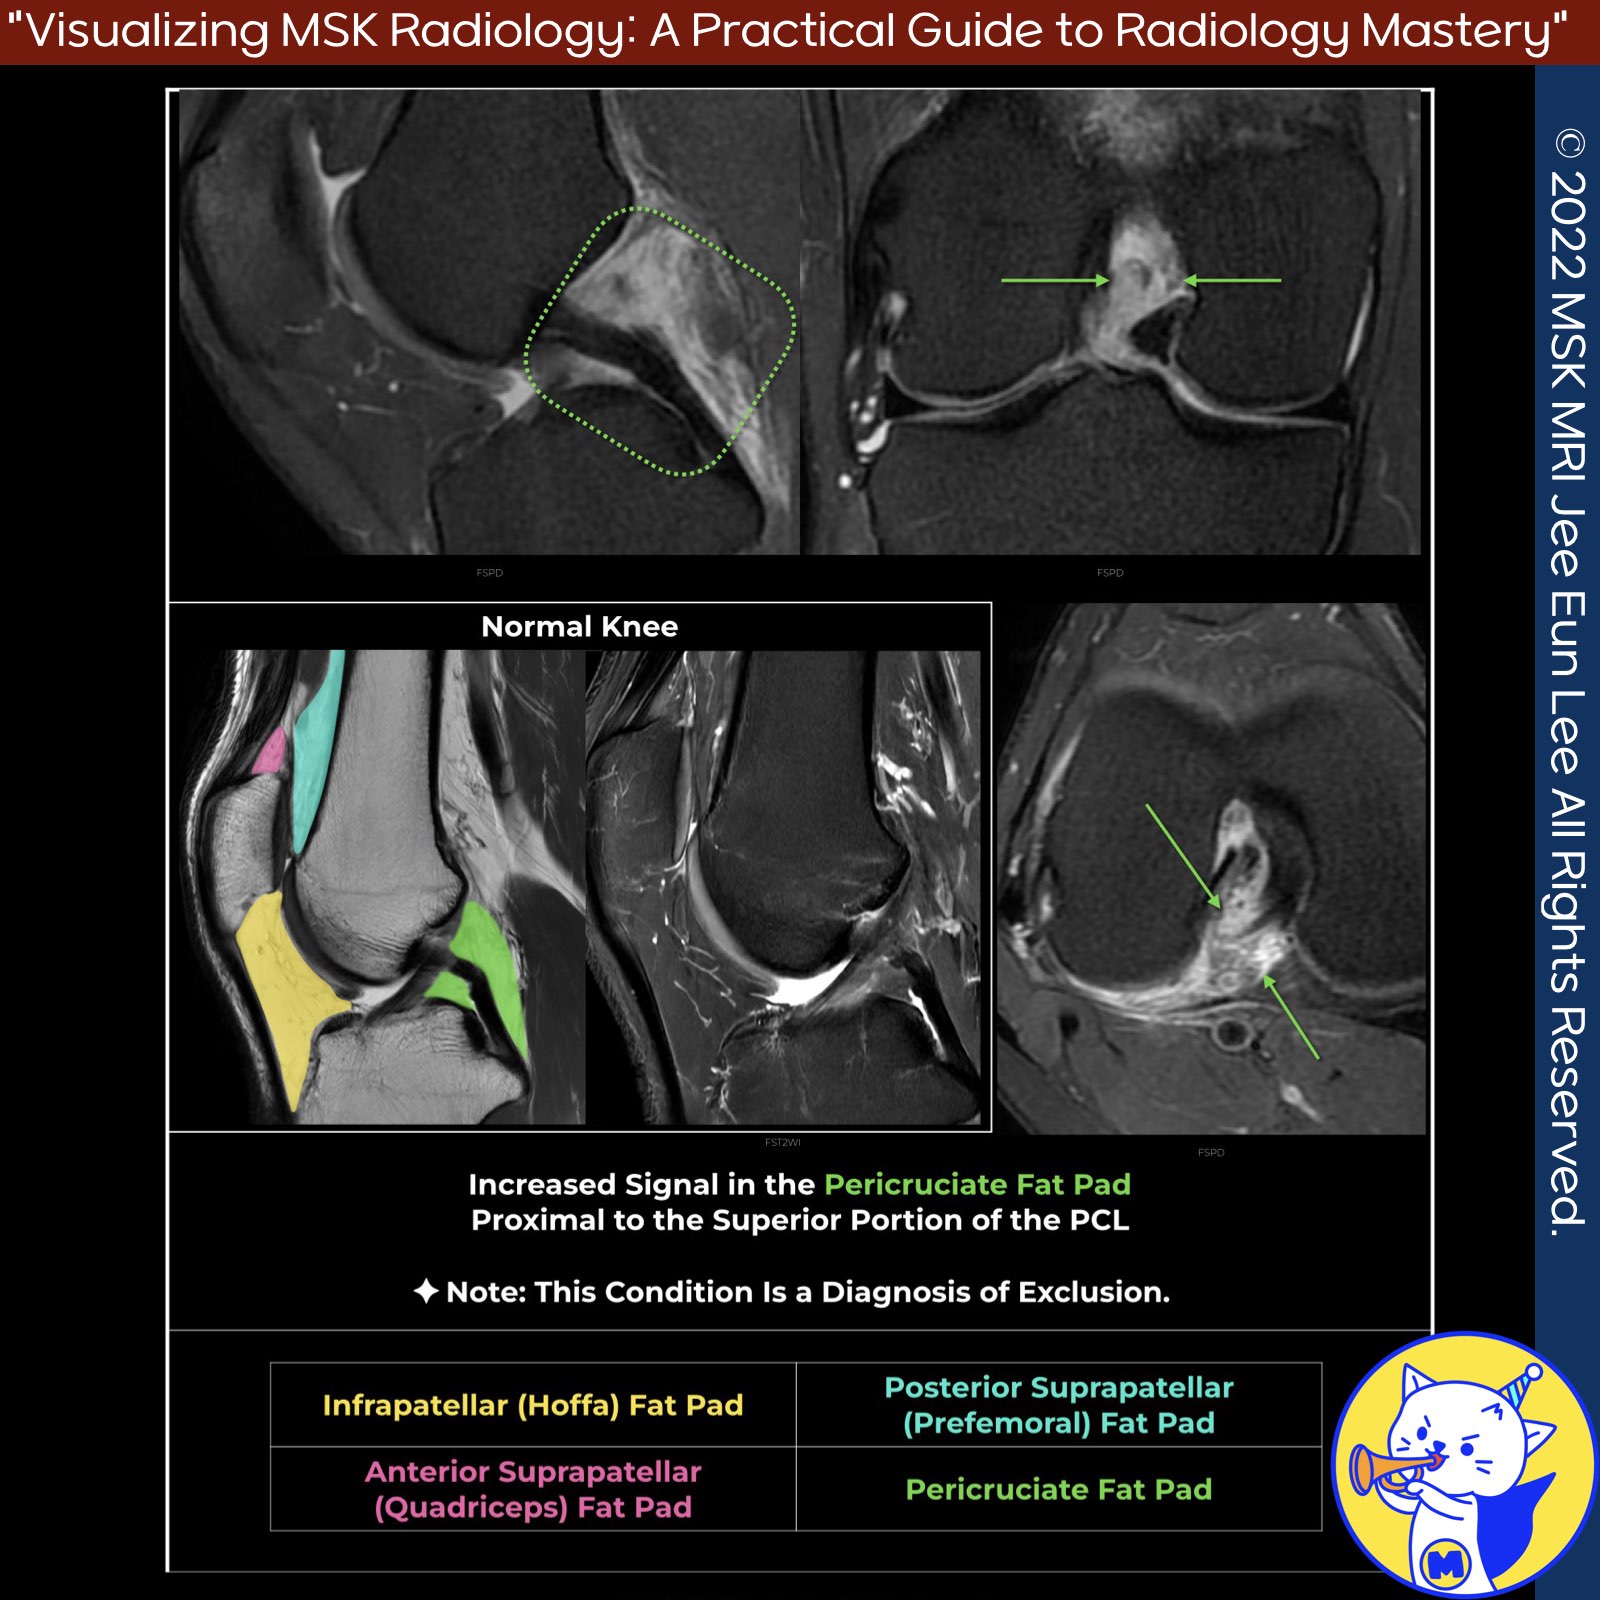

📌Peri-cruciate Fat Pad Inflammation

- Peri-cruciate fat pad inflammation commonly presents as non-specific posterior knee pain, particularly in young individuals with high physical activity levels.

- This condition is often associated with the impingement of the fat pad during knee flexion and is considered an exclusion diagnosis.

✅MRI Findings:

- Poorly defined edema in the peri-cruciate fat pad on fluid-sensitive fat-suppressed sequences.

- Best appreciated on sagittal and axial images.

- The edematous fat pad enhances following contrast administration.